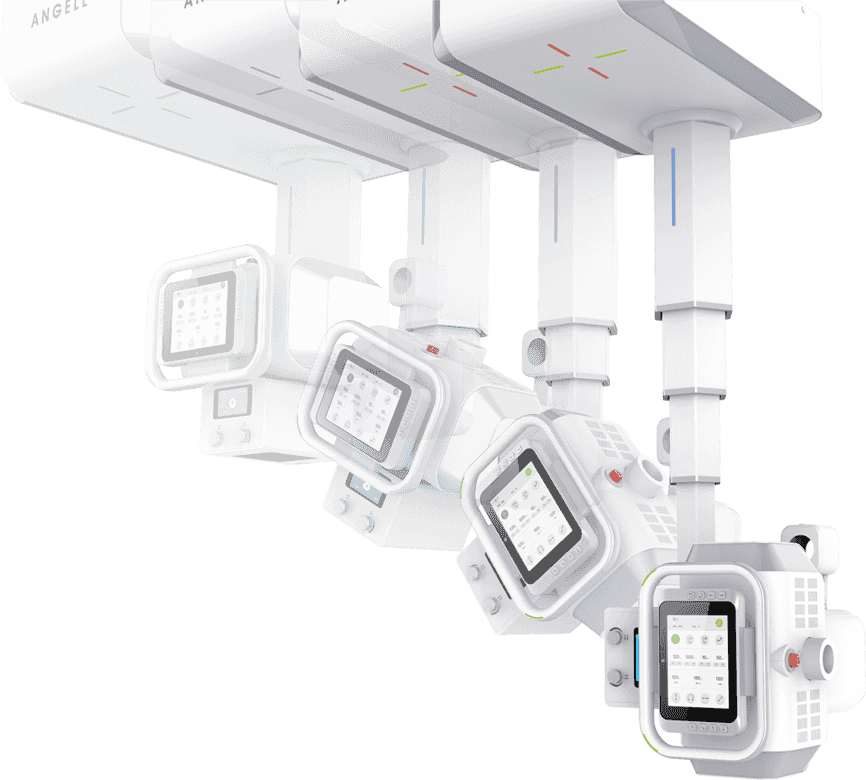

ЧїФЅ¶ЇМ¬іЙПсјјКх

ЧрБъїК±ИЛЙъѕНКЗІ©їЖјјЧФЦчСР·ўµД¶ЇМ¬МЅІвЖчјјКхЈ¬ИГБЩґІјмІйѕЯ±ёїЙКУ»ЇМхјюЈ¬ІўКµПЦїмЛЩёЯЗеµгЖ¬Ј¬

ѕ«ЧјІ¶ЧЅІЎФоЎЈКµПЦґУ¶юО¬ЅвЖКіЙПсµЅЖч№Щ№¦ДЬіЙПсЧЄ±дЈ¬ИГХп¶Пёьѕ«ЧјЎЈ

ёЯЗе¶ЇМ¬

ЖЅ°еМЅІвЖч